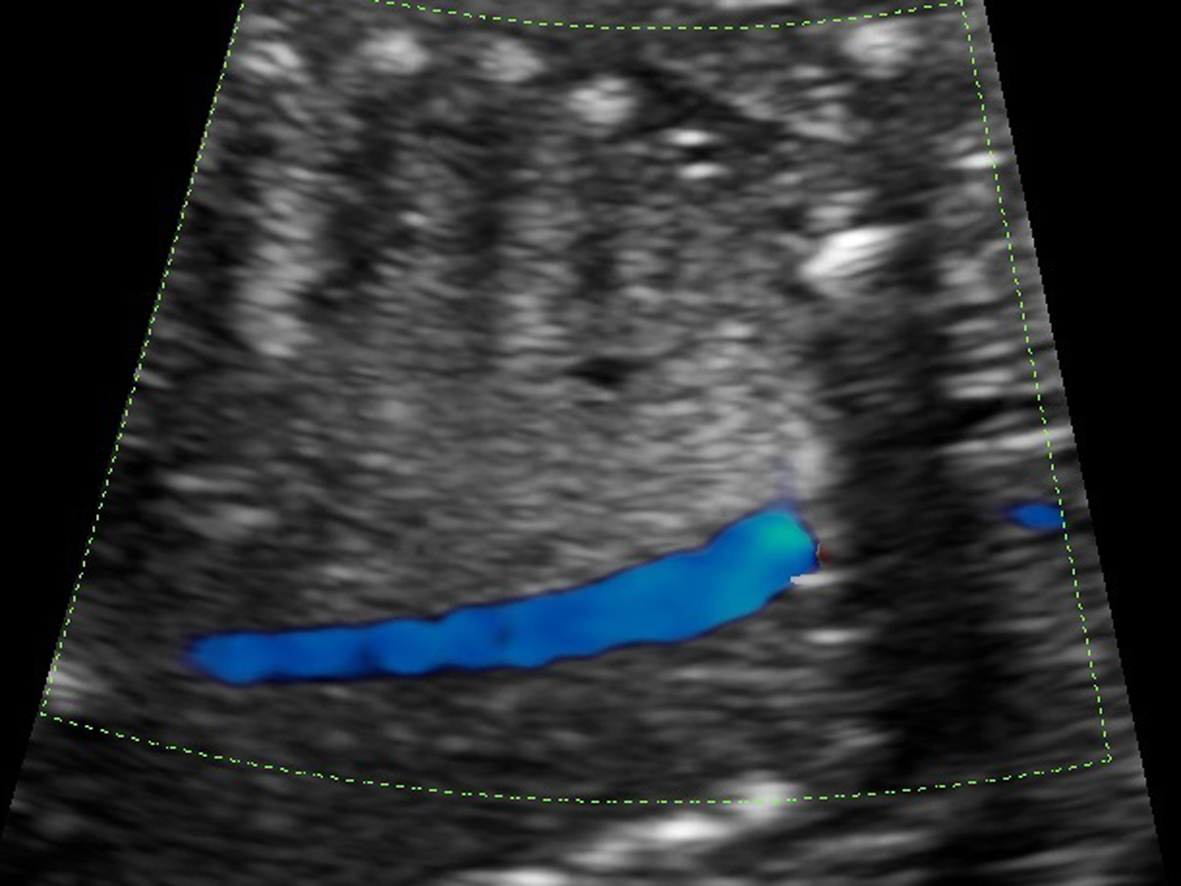

图4 上图同一病例,胸腔占位内部无来自体循环的供血动脉